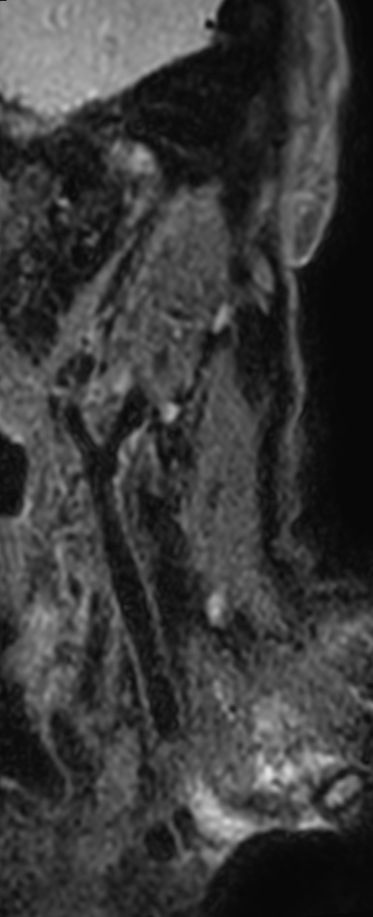

Patient with a neck stenosis. Compressed SENSE is used to shorten the total exam time.

3D T2w TSE Black Blood - Compressed SENSE